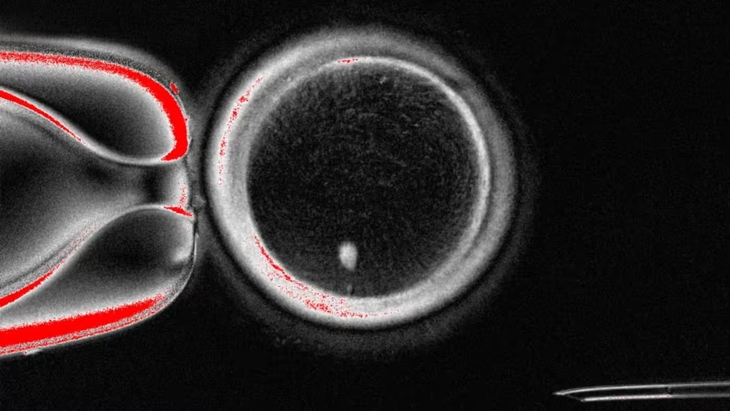

Trứng người chứa DNA từ tế bào da - Ảnh: FINANCIAL TIMES

Theo báo Financial Times, quy trình này bao gồm việc chuyển nhân từ tế bào trưởng thành vào trứng đã loại bỏ nhân, sau đó kích thích phân chia để loại bỏ một nửa số nhiễm sắc thể - điều kiện cần cho quá trình thụ tinh.

Trong khi đó, nhóm nghiên cứu đến từ Đại học Y khoa và Khoa học Oregon (OHSU) áp dụng cách chuyển nhân giữa các tế bào trưởng thành. Quy trình này dựa trên một dạng phân bào mới mà họ đặt tên là “mitomeiosis” - sự kết hợp giữa hai cơ chế phân chia tế bào vốn có trong tự nhiên là nguyên phân và giảm phân, giúp tế bào loại bỏ một nửa số nhiễm sắc thể để sẵn sàng cho thụ tinh.

Tuy vậy, hiệu quả vẫn còn hạn chế. Nhóm nghiên cứu ở OHSU đã tạo ra 82 trứng và thụ tinh bằng tinh trùng qua quá trình thụ tinh trong ống nghiệm (IVF) nhưng chỉ 9% phát triển đến giai đoạn phôi nang, trong khi tỉ lệ tự nhiên là khoảng một phần ba.